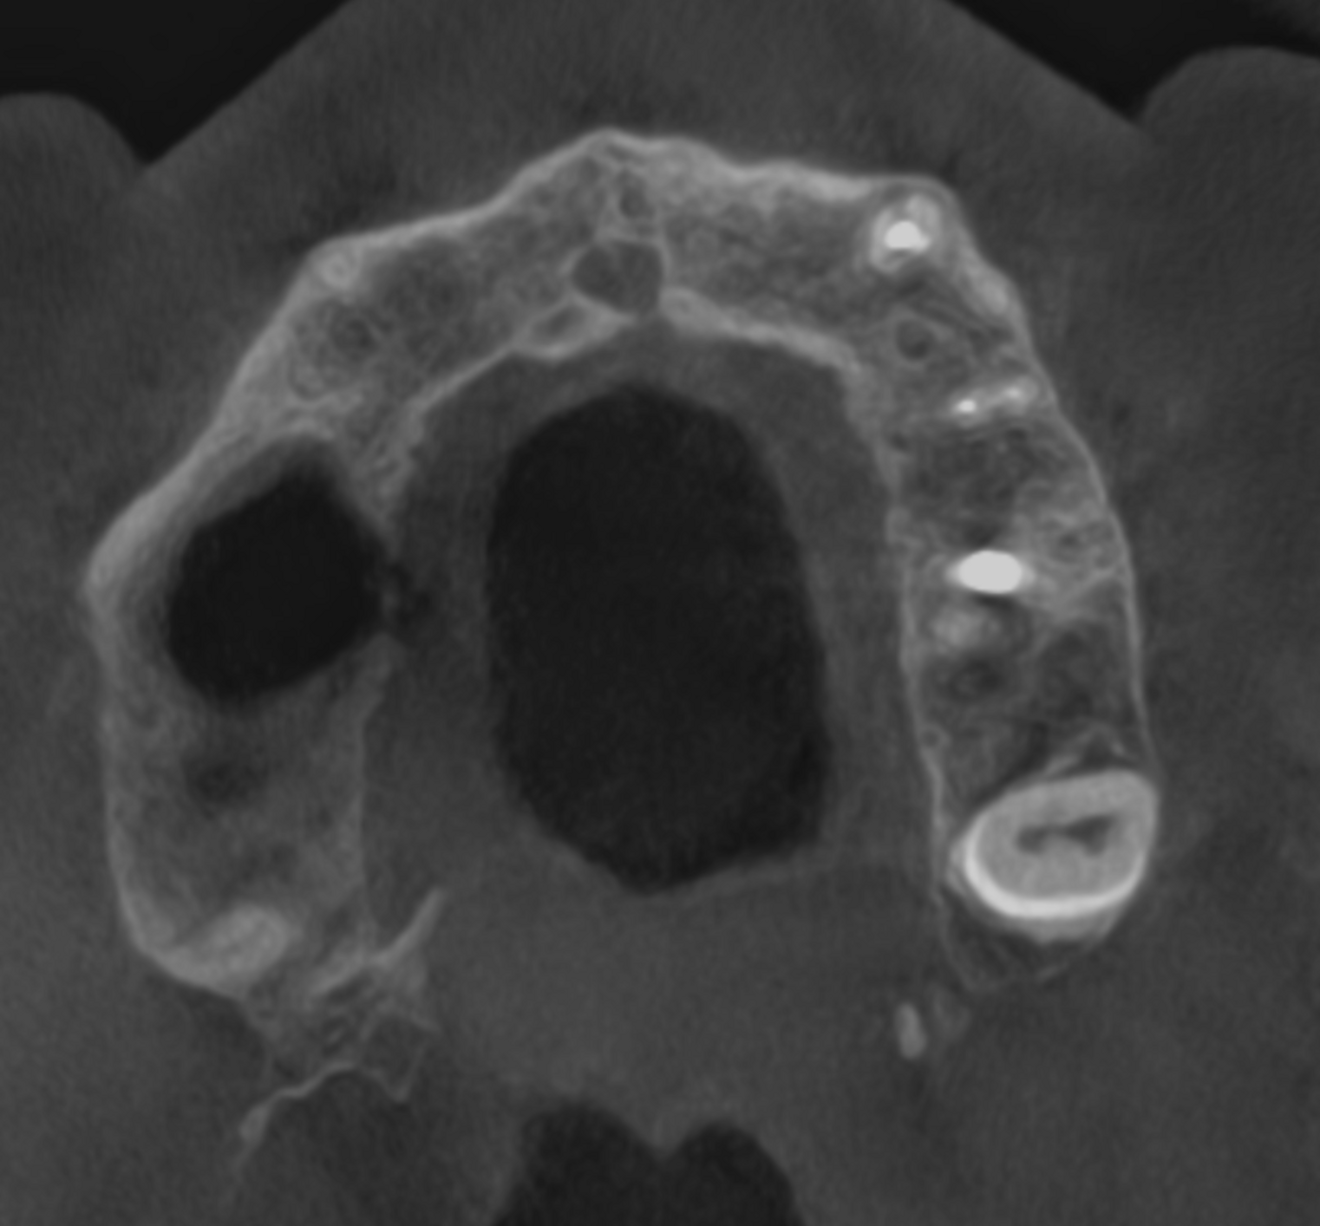

Fig. 5a: Large-volume CBCT scan. Transversal cross-section of the maxilla showing bone loss around the roots of tooth #17 and cortical wall damage.

Fig. 5b: Low-level transversal cross-section of the maxilla showing full involvement of the maxillary sinus.

Right after the opening of the pulp chamber, a strong odour emanated from the oral cavity. This was to be expected given that the CBCT scan showed four relatively wide canals and a large pulp chamber in this second molar—features often associated with necrosis and bacterial accumulation. The pulp chamber was rinsed with copious amounts of sodium hypochlorite. Before shaping of the orifices, the tooth was rinsed with saline, followed by a 17% EDTA solution. I prefer to use the Traverse orifice opener (Kerr Dental) to prepare cone-shaped orifices. Its specialised flute design and heat treatment provide reliable flexibility and strength and support debris removal. The working length was then determined in each canal with a #10 K-file and electronic apex locator. The precise determination was essential in this case because the maxillary bone had been damaged by the inflammation around the apices on both the buccal as well as the palatal sides, penetrating into the maxillary sinus.

As a follow-up, we took a CBCT scan 12 weeks after the obturation, and it clearly showed that both the periapical tissue as well as the paranasal sinuses had recovered fully (Fig. 7). Newly formed cortical and cancellous bone was visible around the buccal and palatal roots (Figs. 8a & b) and extended in the caudal direction. Furthermore, all the paranasal sinuses were clear, and no epithelial widening was visible (Figs. 9a-f).